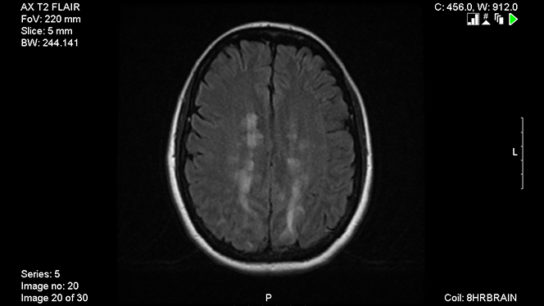

The 2021 MAGNIMS-CMSC-NAIMS provided updated consensus recommendations on MRI use in the management of multiple sclerosis.

A proper MS diagnosis can only be made after obtaining imaging from the entire brain and understanding the clinical context.